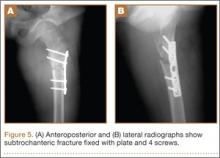

At final follow-up, 6 months after the second surgery, the fracture was healed, and there had been no complications, such as avascular necrosis of the femoral head and leg-length discrepancy (Figures 6A, 6B).